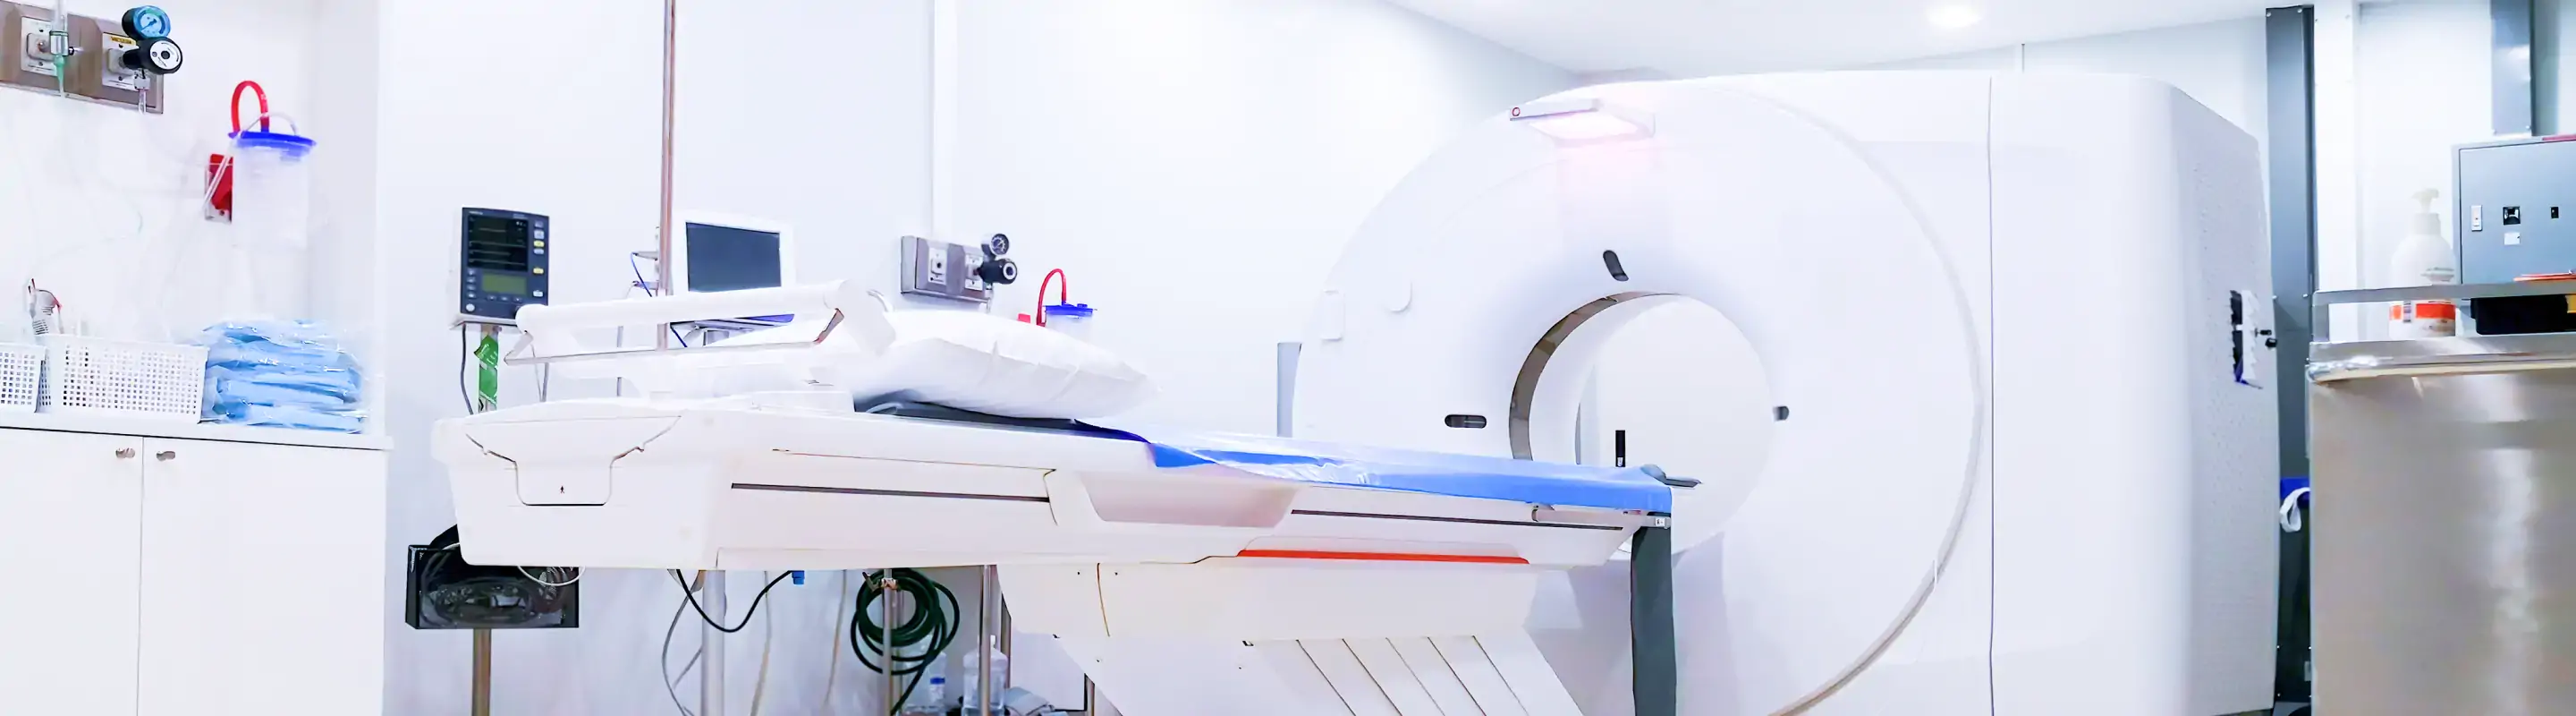

脳ドックとは、MRIを用いて脳および脳血管の状態を精密に評価し、脳卒中や脳腫瘍などの重大な疾患を症状が現れる前に発見するための検診です。ミライエ脳神経クリニックでは、稲沢市のクリニックとしては希少なシアター付きMRIを導入し、短時間・快適な検査と当日の結果説明を実現しています。

当院が導入するMRI装置は、富士フイルムヘルスケア株式会社の「ECHELON Smart ZeroHelium」(1.5テスラ超電導MRIシステム)です。クリニックレベルでこの設備を持つ医療機関は稲沢市を含む地域ではほとんど見られません。

最大の特長は映像シアター機能です。検査中にリラックス系の映像を見ながら撮影を受けていただけるため、閉所の圧迫感が和らぎ、緊張せずに検査に臨んでいただけます。また、脳の撮影は10分以内と非常に短時間で完了します。忙しい方や検査への不安が強い方にも、受け入れやすい環境を整えています。